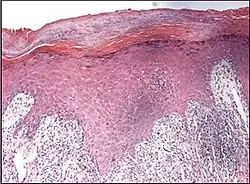

Psoriaform dermatitis

Examining multiple deeper levels is recommended if initial cuts do not correlate well with the clinical history.[2]

Psoriaform dermatitis typically displays:[2]

- Regular epidermal hyperplasia, elongation of the rete ridges, hyperkeratosis, and parakeratosis.

- Usually:A superficial perivascular inflammatory infiltrate

- Often: Thinning of epidermal cells overlying the tips of dermal papillae (suprapapillary plates), and dilated, tortuous blood vessels within these papillae